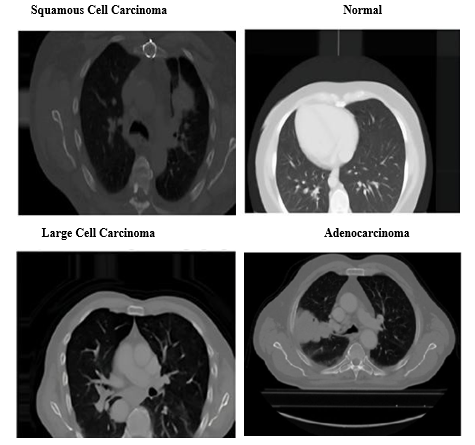

Lung Cancer Classification

To classify chest X-ray images into four categories - Adenocarcinoma, Large Cell Carcinoma, Squamous Cell Carcinoma, and Normal - we implemented deep learning models leveraging pre-trained architectures like VGG16, InceptionV3, and EfficientNetB0. These transfer learning approaches excel at extracting relevant features from medical imaging data, facilitating accurate disease detection. Figure 9 demonstrates this classification process, showing how the model categorizes chest X-ray images into 'Adenocarcinoma', 'Large Cell Carcinoma', 'Squamous Cell Carcinoma', and 'Normal' categories. By utilizing pre-trained architectures for feature extraction, the model achieves heightened accuracy in identifying and distinguishing various lung conditions.